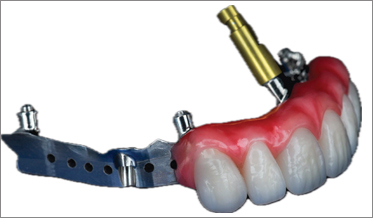

Digital Full-Arch Maxillary Rehabilitation

Isaac Tawil, DDS, MS, Daniel Domingue, DDS, and Scott D. Ganz, DMD